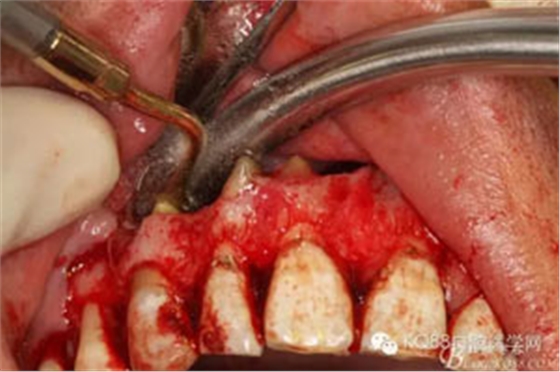

圖9.11/12/13的牙根完全裸露在囊腔內(nèi),13根尖牙膠尖超填過多。

圖10.超聲骨刀行11/12/13根尖切除術(shù)